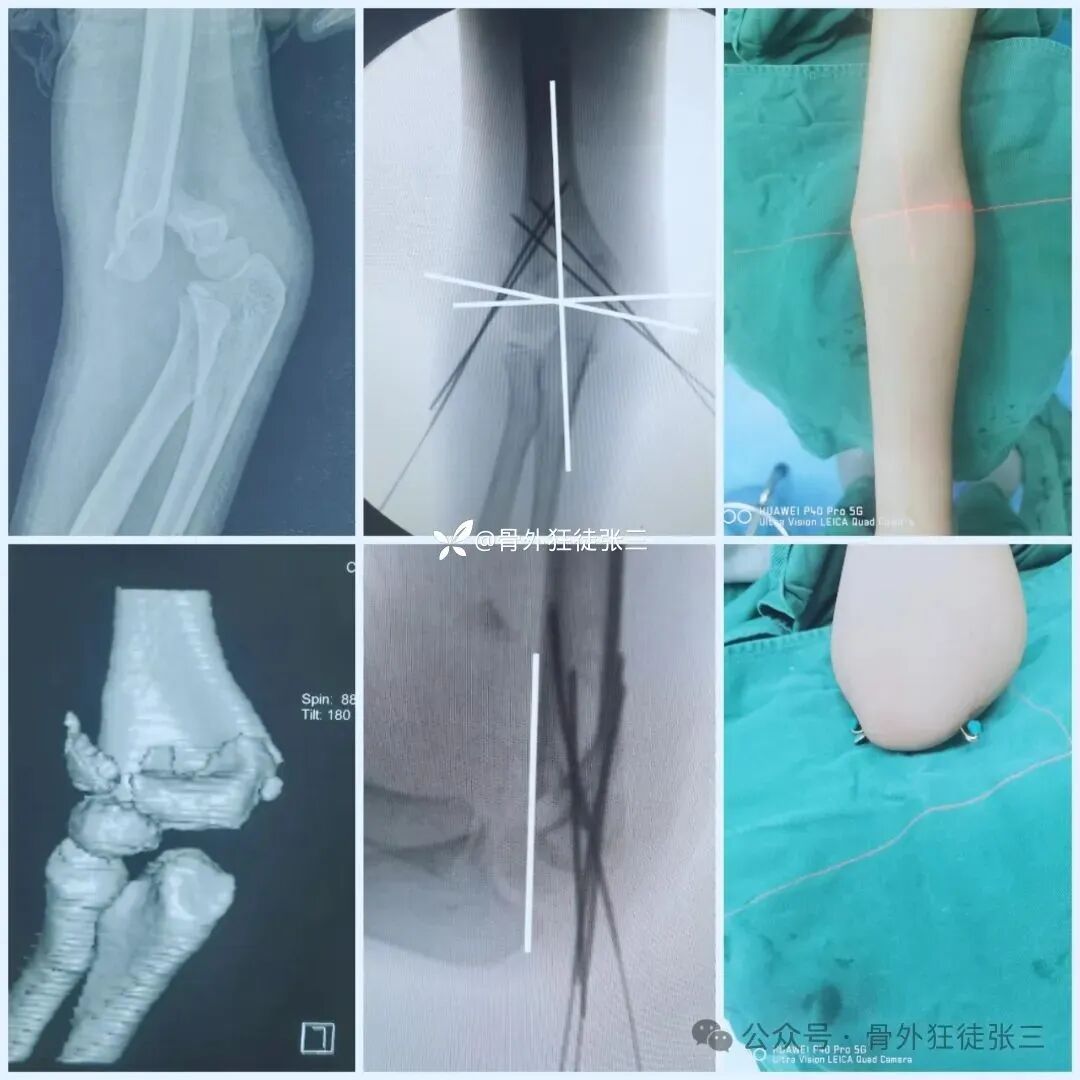

病例2,高位髁上骨折(MDJ骨折)

闭合复位,三枚针发散固定

石膏固定3周

肘关节支具锻炼3周

6周拔针

病例3,低位髁上骨折(全骺分离)

闭合复位,桡侧三枚针发散固定

2周石膏,2周肘关节支具锻炼

4周拔针